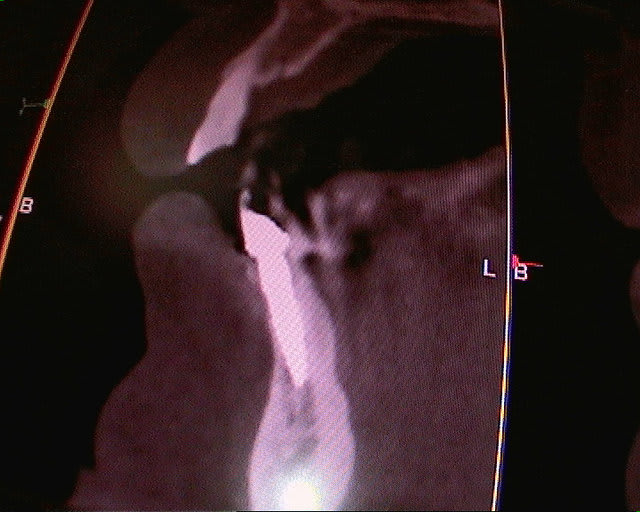

un cas récent os vestibulaire très fin.